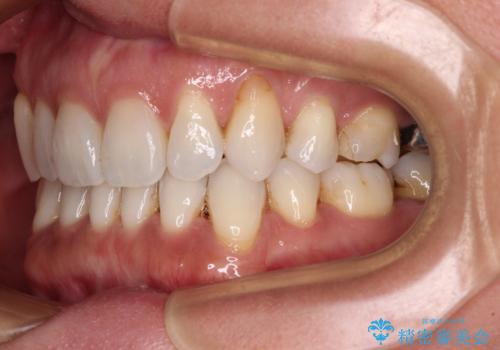

抜歯矯正の後戻りをインビザライン・ライトで解消

- 下顎前歯を中心に、以前行った矯正治療の後戻りが気になるとのことで来院された患者様です。

後戻りは軽度であったため、インビザライン・ライトにて治療を行うこととしました。

矯正治療後は、再度後戻りすることを極力回避するために、下顎前歯の舌側を細いワイヤーを用いて保定することとしました。